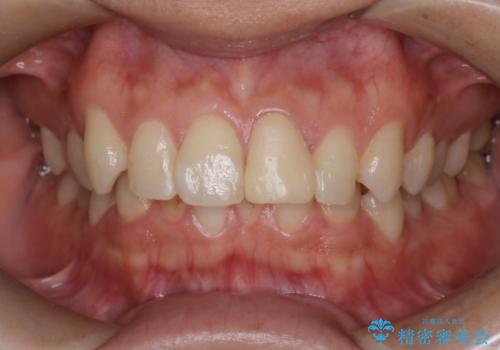

最新の症例

Latest cases